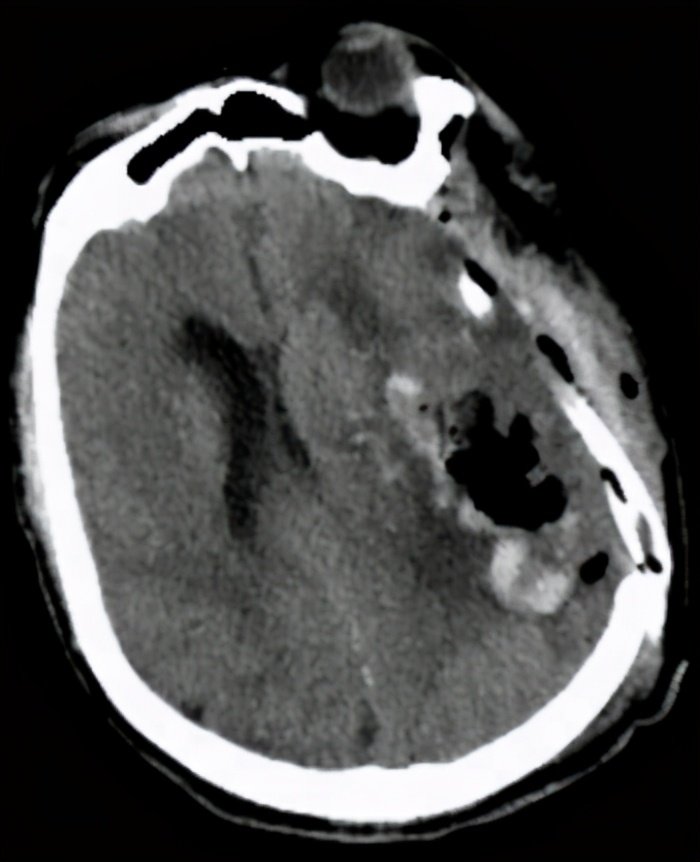

由于术前准备充分,手术过程一切顺利,术中术后生命体征平稳,复查CT脑出血基本清除,达到手术目的。

术后